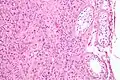

![]() Histological section through testicular parenchyma of a boar. 1 Lumen of convoluted part of the seminiferous tubules, 2 spermatids, 3 spermatocytes, 4 spermatogonia, 5 Sertoli cell, 6 myofibroblasts, 7 Leydig cells, 8 capillaries | |

Leydig cells, also known as interstitial cells of the testes and interstitial cells of Leydig, are found adjacent to the seminiferous tubules in the testicle and produce testosterone in the presence of luteinizing hormone (LH).[1][2] They are polyhedral in shape and have a large, prominent nucleus, an eosinophilic cytoplasm, and numerous lipid-filled vesicles.[3]

The mammalian Leydig cell is a polyhedral epithelioid cell with a single eccentrically located ovoid nucleus. The nucleus contains one to three prominent nucleoli and large amounts of dark-staining peripheral heterochromatin. The acidophilic cytoplasm usually contains numerous membrane-bound lipid droplets and large amounts of smooth endoplasmic reticulum (SER).[4] Besides the abundance of SER with scattered patches of rough endoplasmic reticulum, several mitochondria are also prominent within the cytoplasm. Reinke crystals have lipofuscin pigment and rod-shaped crystal-like structures 3 to 20 micrometres in diameter.[5]